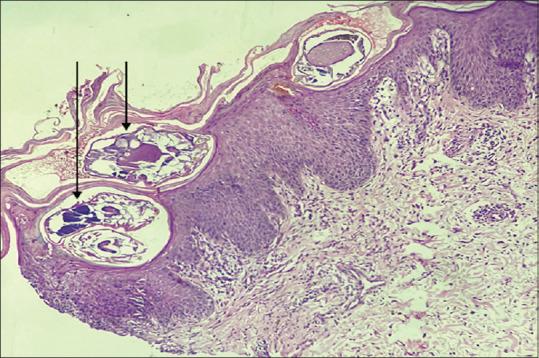

Dermoscopy of Crusted Scabies: Revisiting the New and Old Signs.

Indian Dermatol Online J. 2022 Dec 14;14(2):279-280. doi: 10.4103/idoj.idoj_263_22. eCollection 2023 Mar-Apr.